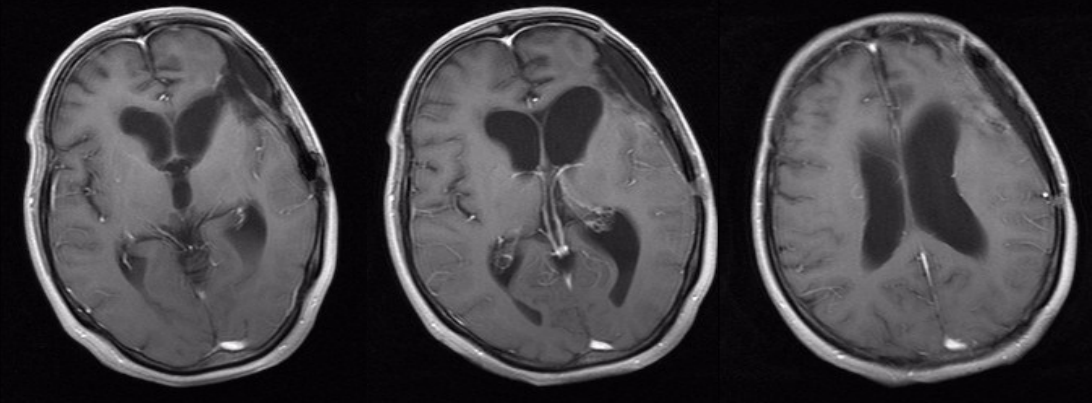

术后头颅CT